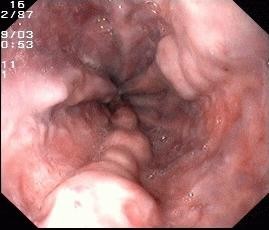

⑧静脉套扎及组织胶注射

肝硬化食管静脉曲张一旦破裂往往造成致命的大出血。内镜下食管静脉曲张套扎术(EVL)是对食管下段曲张静脉逐一结扎,使其缺血狭窄、静脉闭塞,增加静脉周围纤维覆盖,从而使曲张静脉消失,达到止血和预防再出血。

食管静脉曲张

食管静脉破裂出血

食管静脉曲张套扎进行中

食管静脉曲张套扎进行中近观

食管静脉曲张套扎恢复后

EVL是抢救食管静脉曲张破裂大出血、预防再出血的首选方法,该技术具有快捷、简单、并发症少、疗效高的特点 。EVL是治疗食管静脉曲张的一种新技术和新方法,我院消化内科开展EVL 1O年,多位教授具有丰富临床经验,每年救治了无数肝硬化食管胃底静脉曲张破裂大出血患者生命。

食管曲张静脉的自然病程

肝硬化患者每年有5%-15%发展为食管静脉曲张,静脉曲张一旦出现每年增长4%-10%,三分之一静脉曲张患者发出曲张脉破裂出血,每次破裂出血导致20%-30%的患者死亡,未行治疗的曲张静脉破裂出血患者,首次出血后1年内死亡率达70%。